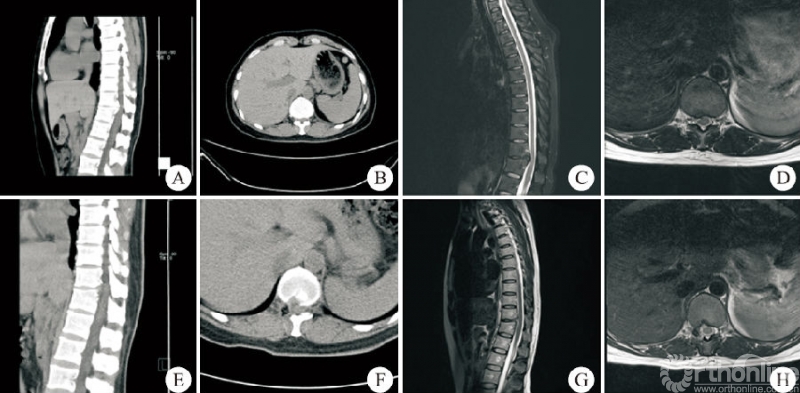

所有患者的手术由同一位术者完成,手术均顺利完成,无硬膜外血肿、切口感染及术后瘫痪者。37例患者中男14例,女23例;年龄31~82岁,平均(57.6±11.8)岁。上胸段(T1−T4)1例,中胸段(T5−T9)7例,下胸段(T10−T12)29例。24例采用俯卧位,13例采用侧卧位。平均住院时间(7.2±1.6)d,平均手术时长(96.5±20.0)min。平均出血量(41.9±10.8)mL。24例俯卧位手术患者均为OLF,做“漂浮”处理的3例,2例患者术中硬膜破裂(图3)。13例侧卧位手术患者中TDH3例,OPLL5例,OLF+OPLL5例,做“漂浮”处理的1例,2例患者术中硬膜破裂(图4)。术后影像学检查示椎管减压充分,致压物被完全去除。

男,46岁,T11−T12黄韧带骨化合并椎管狭窄,行俯卧位经皮内镜可视化环锯椎管减压术。A、B:术前CT矢状位和横断位示T11−T12融合型黄韧带钙化;C、D:术前MRI示脊髓严重受压合并信号改变;E、F:术后CT矢状位和横断位示钙化的黄韧带完全去除椎板充分扩大减压;G、H:术后MRI示脊髓不受压硬膜完全鼓起。图3 T11−T12俯卧位胸椎后入路术前与术后影像学资料